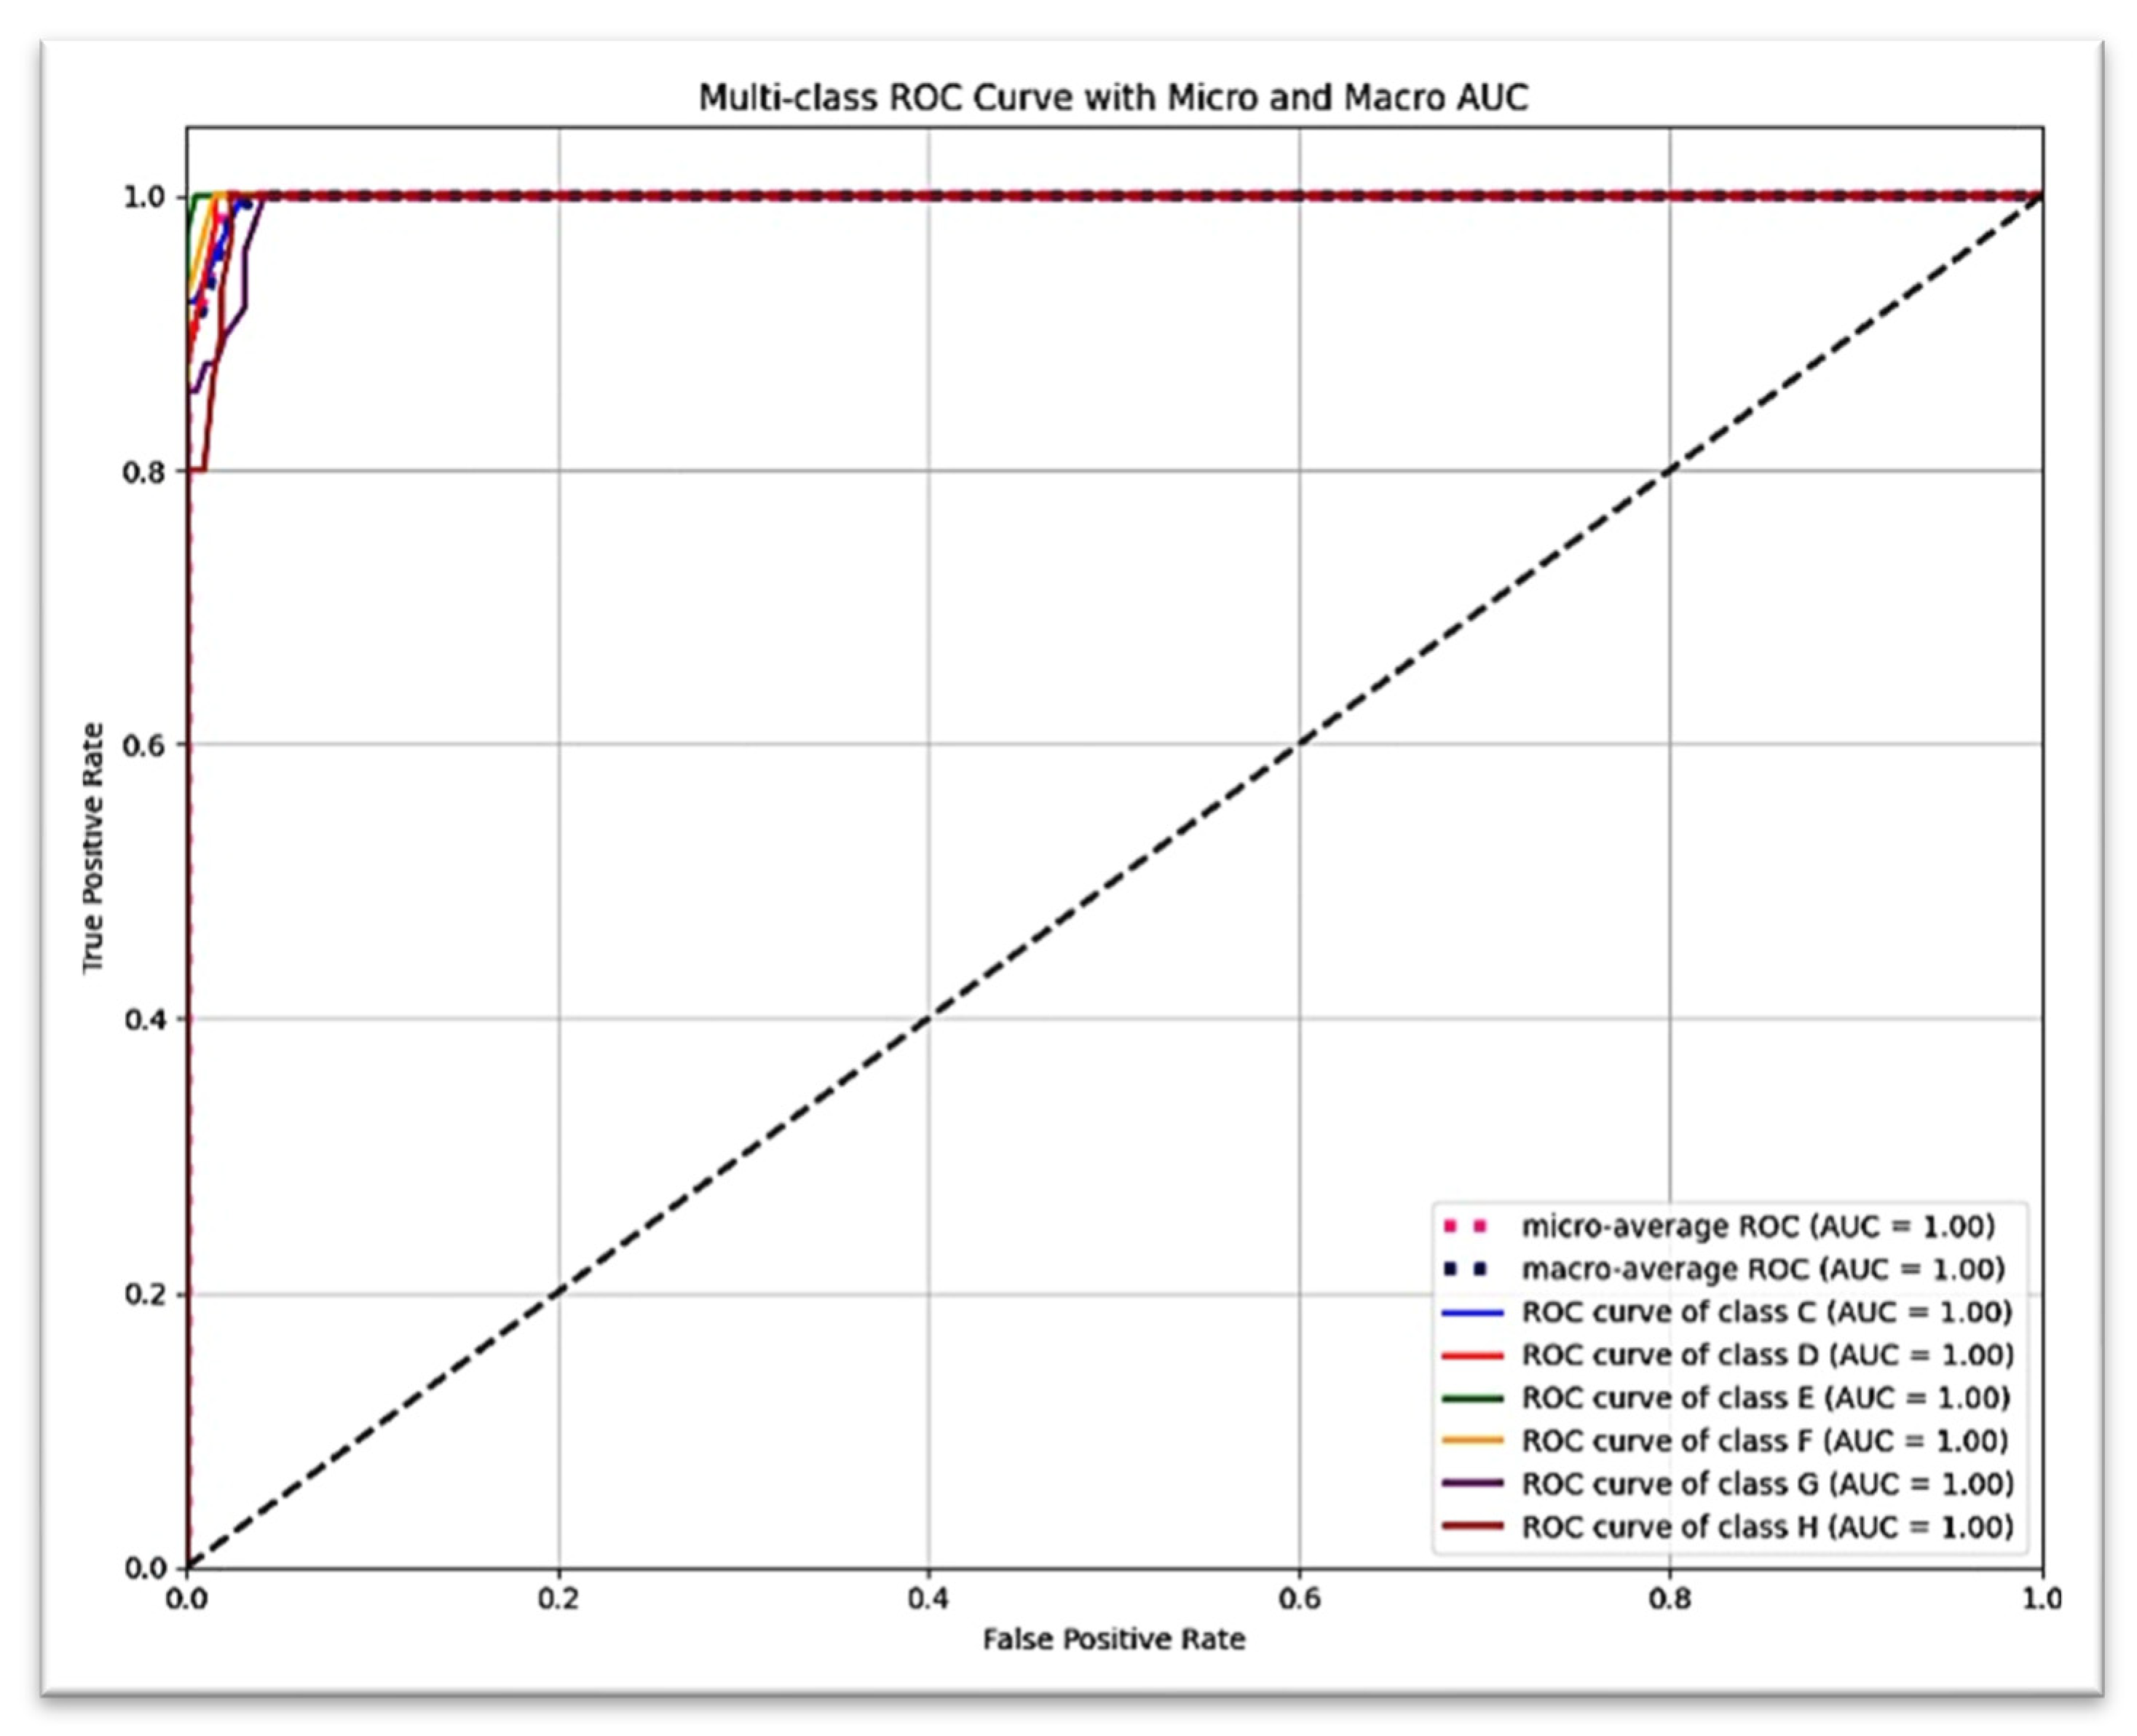

Figure 5 presents the detailed classification results for each of the six Demirjian stages using a confusion matrix, which reveals that the vast majority of true positive predictions are located along the diagonal. The ROC curve, shown in

Figure 6, revealed an AUC = 1.00 (with the exception of stage G: AUC = 0.99), suggesting excellent discriminatory power (stages C, D, E, F, and H: AUC = 1.00).